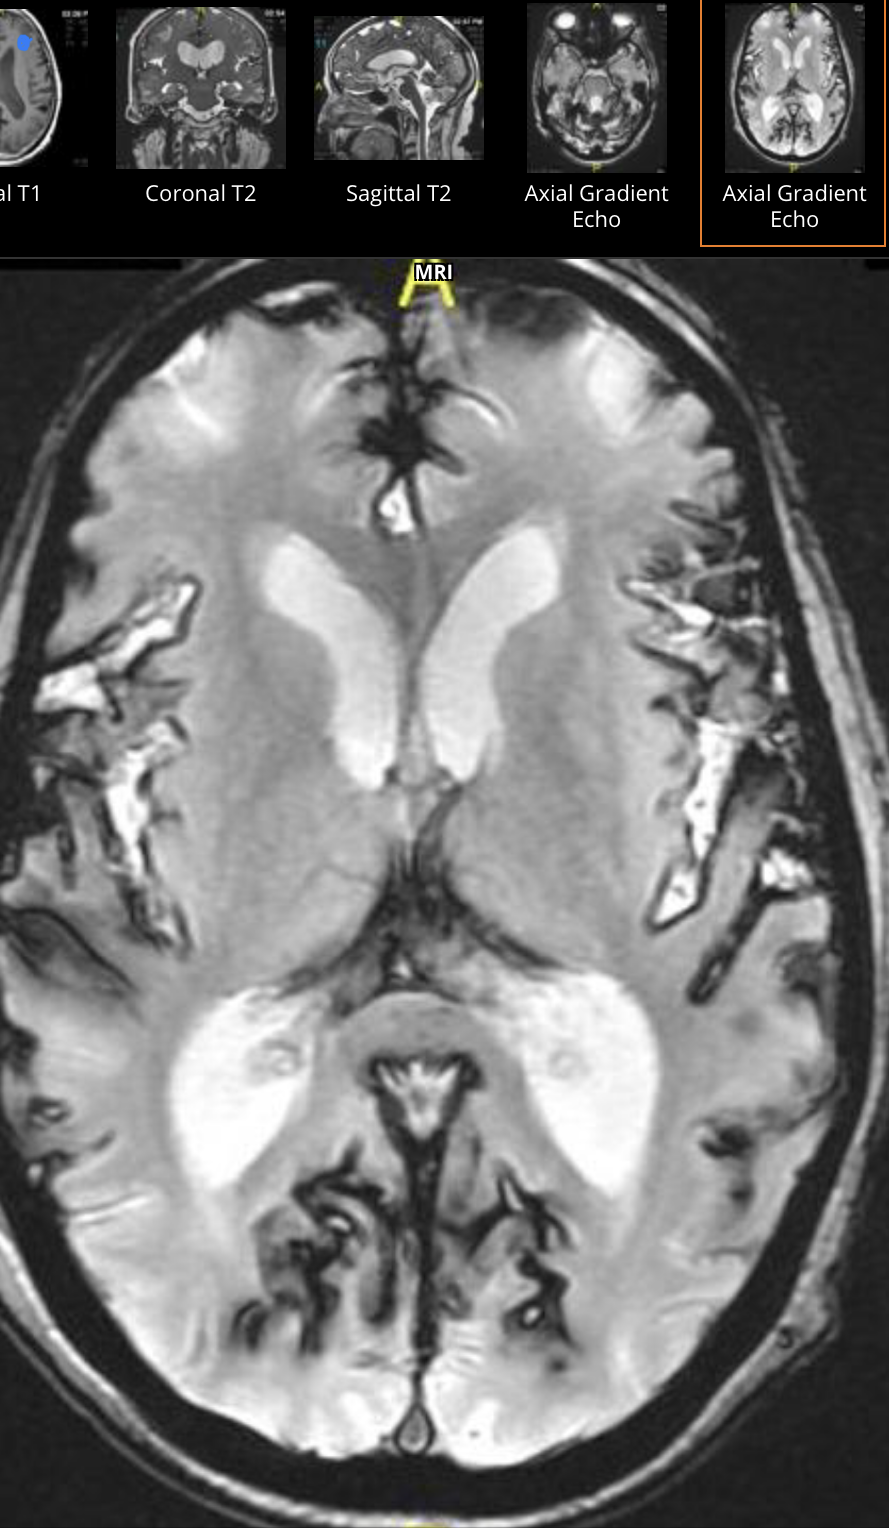

SUPERFICIAL SIDEROSIS - what is it?

SIDEROSIS

(symptoms: vertigo, tinnitus)